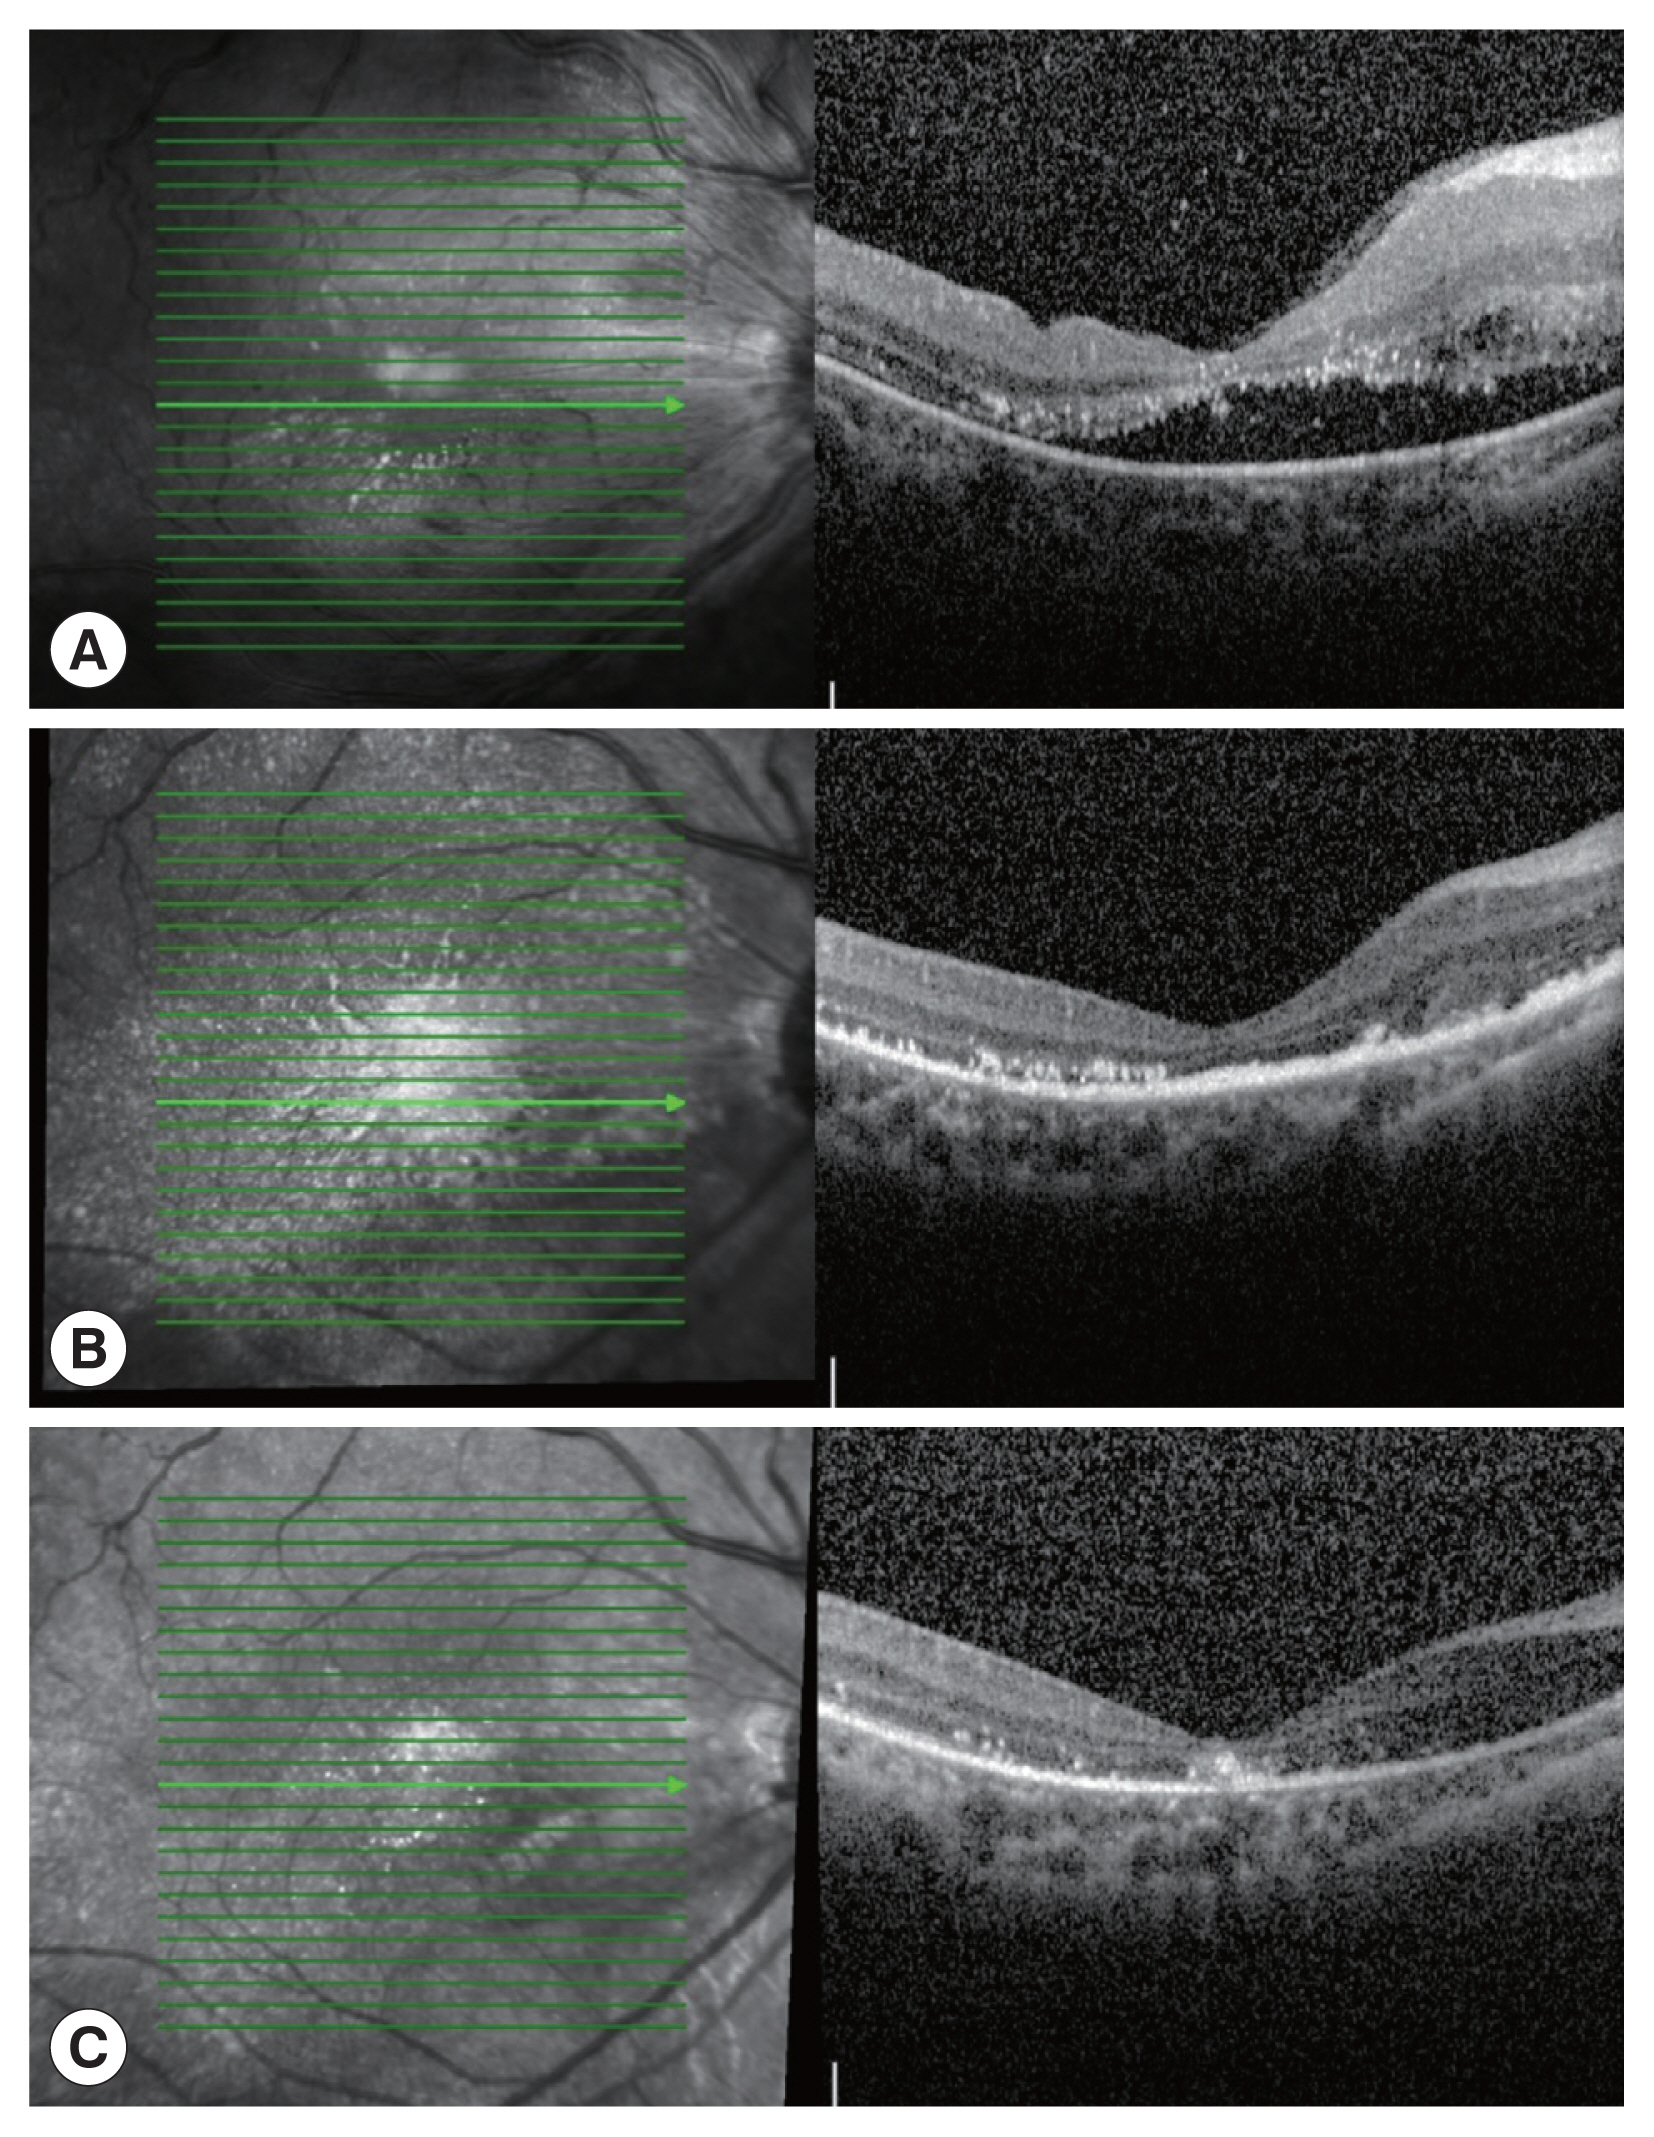

Fig. 2

(A) A hyporreflective area between the neuroepithelium and pigment epithelium in the macular area was observed. (B) The retina was reattached, while retinal exudates remained 1 month post injection. (C) Subretinal exudation improved significantly 8 months post-injection.

The patient was treated with albendazole 400 mg daily for 5 days as laboratory investigations confirmed infection with toxocariasis. He was administered the first injection of intravitreal DEX implants. At 1-week post-DEX implant injection, fundus examination showed an improved disc edema (Fig. 2B). Neuroepithelial layer detachment was recovered, and the retinal exudates was decreased in OCT images (Fig. 2B).

At 8 months post-DEX implant injection, the patient had a BCVA of 20/400 and IOP of 16 mmHg. The fundus examination revealed retinal blood vessel whitening and slightly edematous inferior retina (Fig. 1D). OCT showed that the subretinal exudation was improved significantly (Fig. 2C). Retinal hemorrhage and vascular tortuosity were improved. Retinal exudation was decreased in FFA (Fig. 3B). Next day, we administered the injections of intravitreal DEX implant again to the patient.